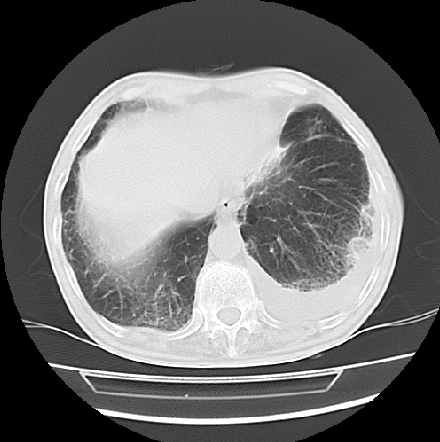

以下是引用ct诊断高手在2009-5-29 13:50:00的发言:[br]考虑左侧中央型肺癌,阻塞性肺炎伴肺不张。纵隔淋巴结转移。慢支 肺间质纤维化肺气肿。左侧胸腔积液。左侧肋骨转移?

以下是引用hhcckk在2009-5-29 14:58:00的发言:[br]左上周围型肺癌,左肺门、纵隔淋巴结转移,左侧胸腔积液,左侧肋骨转移[br]